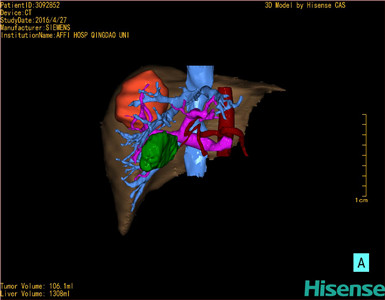

CT结果输入海信CAS系统后行3D重建及手术规划后,于2016-5-14全麻下行“肝VII+VIII段切除术”手术治疗:

术前三维重建及手术方案设计:

将0.625mm双源薄层CT资料的静脉期和动脉期Dicom格式文件导入海信CAS系统。

通过调节窗宽窗位调整CT序号,对肿瘤,肝实质,胆囊,下腔静脉,肿瘤,肝动脉、门静脉及肝静脉等进行三维重建;系统自动计算肿瘤体积和肝脏体积。

模拟手术操作,自动计算切除肿瘤体积。肝脏体积为1308ml,肿瘤体积为106.1ml,肿瘤体积为肝脏体积的8.1%,通过比对40-50岁正常肝脏体积为1368.38±279.24 ml,通过术前模拟手术,精准判断切除后剩余肝脏体积能耐受,避免肝衰竭发生。

术前手术方案的规划。

术前三维重建:

重建图片